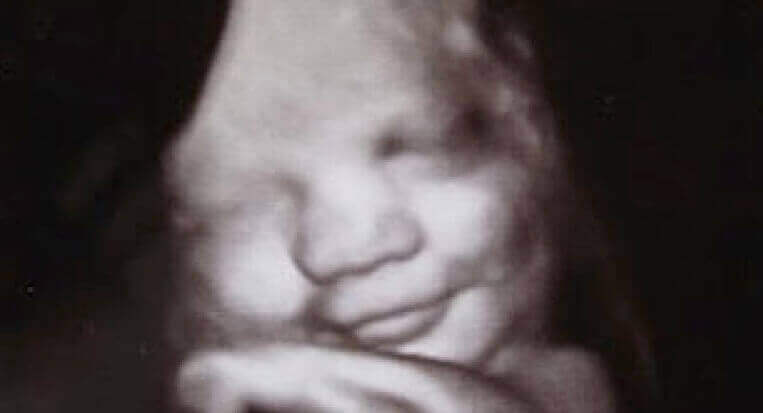

Poucas condições desprendem tanto mistério como as emoções. É verdade que fazem parte de nossa cultura, de nossa educação, sexo ou país de origem. No entanto, não é menos verdade que já vem integradas em nossa base genética. Para demonstrar isso, as universidades de Durham e Lancaster (Inglaterra) realizaram um fascinante estudo onde se pode ver que os fetos já expressam uma pequena variedade de emoções dentro do útero materno.